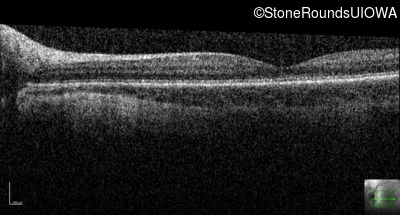

Age at visit: 7 years

This 7 year old boy had nystagmus first noticed at 4 months of age.

Age at visit: 11 years

Blue Cone Monochromacy L/M OPSIN Cluster Promoter Deletion LCR   XL